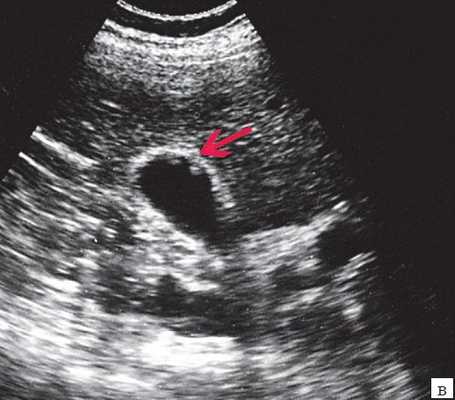

Ультрасонография является эффективным средством выявления полиповидной формы холестероза 7. Традиционной считается следующая сонографическая характеристика холестериновых полипов: неподвижные гиперэхогенные структуры, которые не дают акустической тени и прикрепляются к стенке желчного пузыря. Контуры таких образований, как правило, ровные, а размеры таких образований различны, чаще не превышают 10 мм (рис. 2).

a) Одиночный полип в желчном пузыре (гиперэхогенное пристеночное неподвижное образование, с ровными контурами, без акустической тени).

б) Одиночный полип в желчном пузыре.

в) Полиповидно-сетчатая форма холестероза, полипы размерами до 5 мм, повышенной эхогенности.

г) Одиночный полип в желчном пузыре.

Однако, по некоторым данным, размеры холестериновых полипов могут быть более 20 мм. Кроме того, полипы больших размеров (в 7% от общего числа) могут иметь пониженную эхогенность и фестончатый контур.

Мелкие холестериновые включения, образующие диффузную сеточку в толще подслизистого слоя размерами 1-2 мм, выглядят как локальное утолщение или уплотнение стенки желчного пузыря и в некоторых случаях (см. рис. 2) вызывают реверберацию (эхографический симптом "хвост кометы").